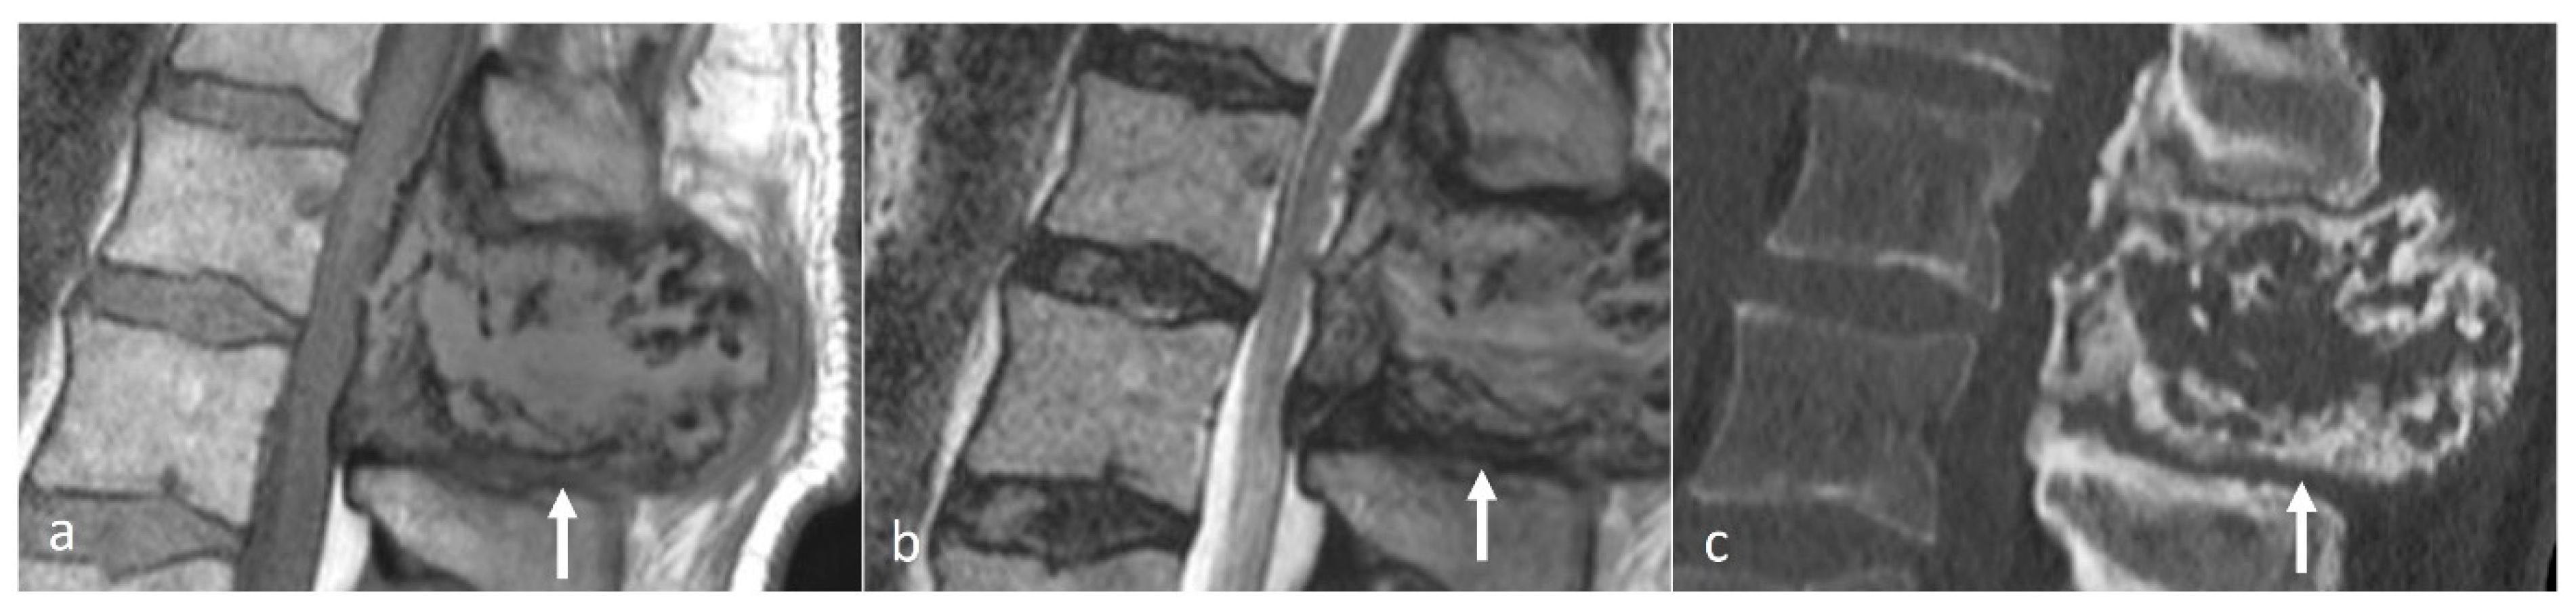

Osteoid osteomas (OOs) account for 10–14% of primary vertebral tumours. The majority are seen in the lumbar spine, followed by the cervical and thoracic spine. Given their predilection for the posterior elements, involvement of the spinous process is not uncommon [15,16]. MRI is sensitive and may show marrow oedema; however, the oedema can obscure the nidus, which can be a potential pitfall. On MRI, the nidus when seen is of low to intermediate T1 signal, ofvariable T2 signal with areas of signal void due to mineralisation (Figure 2a). The nidus may also show variable enhancement on post-contrast imaging [15,16]. Lesions may be occult on a radiograph. The presence of sclerotic reactive bone surrounding a lucent nidus is a typical feature on CT, although the latter may not always be present (Figure 2b). A central sclerotic dot may also be present. The nidus is typically <1.5 to 2 cm in diameter.

Figure 2.

Sagittal STIR (a) and CT (b) images demonstrating a thoracic spinous process osteoid osteoma (white arrows). Note the presence of reactive marrow oedema on the STIR sequence. The sclerotic reactive bone is well delineated on CT, although the lucent nidus may not always be present as in this case.